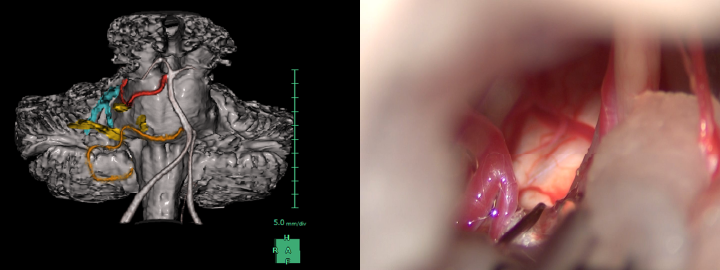

三叉神経痛や片側顔面けいれんの診断に至り、根治を目指す場合や内科的治療で十分な改善が得られない場合に、微小血管減圧術(MVD)を検討します。手術では耳の後ろの骨を小さく開頭し、手術用顕微鏡で原因血管を特定し、神経から慎重に剥離して移動させます。この手術は症状の根本原因を取り除く治療であり、術後早期に症状の緩和や消失が得られる場合が多いです。手術に際しては、聴力障害や顔面神経麻痺などの合併症を回避するため、術中モニタリングを活用しながら、安全で確実な手術の遂行に努めています。